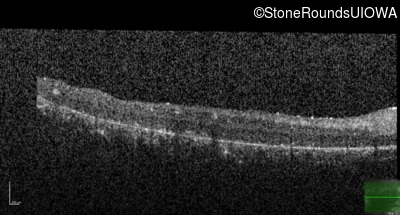

Age at visit: 8 years

This 8 year old girl had normal vision until age 6 when she failed a school vision screening. That year, she was able to play softball well, but this year she often loses sight of the ball and is often hit by it.